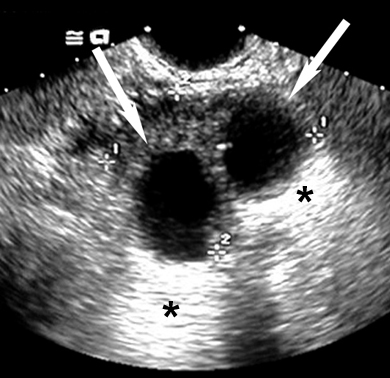

Renal cyst presents as a "renal mass" in imaging procedures.

Ultrasound can easily distinguish renal cysts from mass lesions.

Simple Anechoic Renal Cysts

Arrows points to cyst.

* Points to  good through transmission of echoes behind the cyst.